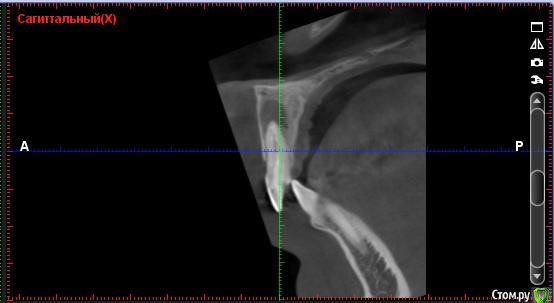

Andre_ Опубликовано 22 октября, 2015 Поделиться Опубликовано 22 октября, 2015 Верхней челюсти кисты, если быть точнее. Терапевт пробовал перепроходить - цемент. Пациент - молодой парень, крайне хочется, чтобы ушёл с зубами, хотя бы временными. Какой бы вы план действий преложили? Ссылка на комментарий

DmitrySH Опубликовано 22 октября, 2015 Поделиться Опубликовано 22 октября, 2015 Есть смысл пробовать ещё? Да вы еще и не попробовали толком. Передайте пациента эндодонтисту со скопом и будет всем счастье.Под микроскопом цемент расломбировать в прямом канале.. вообще никаких проблем. Поводов для хирургии на данный момент нет. 7 Ссылка на комментарий

Дмитрий Никитюк Опубликовано 23 октября, 2015 Поделиться Опубликовано 23 октября, 2015 Забудьте про диагноз "киста", это моветон. Подобные диагнозы можно ставить только после гистологии. Есть диагноз "апикальный периодонтит". Соответственно и подход к лечению при таком диагнозе не предполагает на первом этапе никакой хирургии, только ретрит. Затем динамическое наблюдение и принятие решения по хирургическому лечению, в случае неэффективности консервативного. 5 Ссылка на комментарий